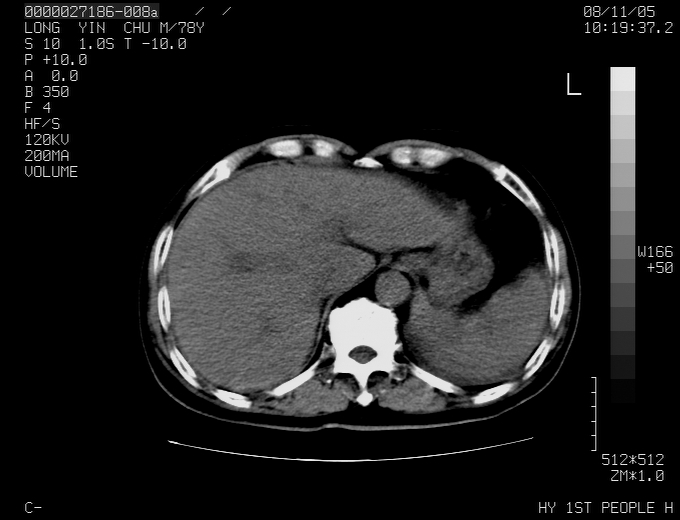

腹胀,腹痛就诊,男性,78岁,外院b超未见异常。

肝ca,脾肾转移

支持脾肾转移瘤,双侧胸腔积液。

考虑弥漫性肝癌并脾及双肾转移.双侧胸水.

图片质量欠佳:多考虑:左侧肾癌。脾脏转移!胸膜转移!

肝脾肾转移瘤可能性大,左肾不除外梗塞,双侧胸水

考虑肝癌并双肾及脾脏转移;双侧胸腔积液。